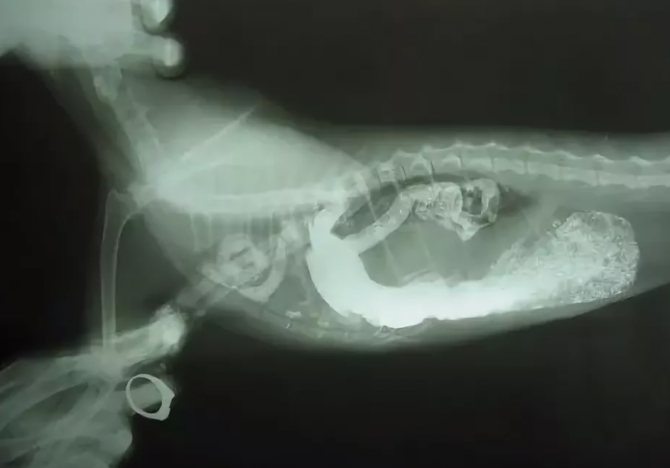

с данной патологией усатые питомцы могут уже рождаться, но в большинстве случаев они приобретенные вследствие серьезных травм, падений с высоты, ударов и т.п. Из-за повышения внутрибрюшного давления кишечник начинает усиленно давить на диафрагму, прорывая ее все сильнее и давя на органы грудной полости. Очень сложно диагностировать, т.к. из-за особенностей анатомического строения у кошек даже на УЗИ и рентгене точно грыжевого мешка не видно, кроме затемнения общего плана. Чтобы убедиться, что у кошки именно диафрагмальная грыжа, ее пытаются накормить контрастным веществом (каша с барием) и сделать в нужное время рентген. Опасный вид патологии, может привести к гибели питомца.

Причина заболевания устанавливается при клиническом осмотре. Информативен сбор анамнеза. Важно выяснить, была ли у животного травма, если проникающего ранения не произошло. В отдельных ситуациях владелец животного обращается за ветеринарной помощью через несколько дней, а иногда и недель после происшествия. Для уточнения диагноза ветеринарный врач назначает УЗИ, а также рентгенограмму с контрастными веществами.

Диафрагмальная грыжа может быть обнаружена рентгеновским снимком. Точность диагноза повысит бариевый контраст, его вводят в организм питомца с помощью скармливания ему пищи, куда добавлен порошок. Это позволит определить локализацию петель кишечника. Также допустимо проведение электрокардиографии, чтобы проконтролировать нормальность функционирования сердца у кошки.